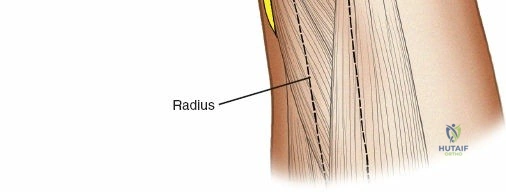

Radius Safe Zones

* Proximal Third: The posterior interosseous nerve (PIN) courses through the supinator muscle. Pin placement in the proximal radius is highly hazardous and generally avoided unless absolutely necessary. If required, a formal dorsal approach (Thompson) is used to visualize and protect the PIN.

* Middle Third: Pins can be placed dorsolaterally. The superficial radial nerve (SRN) and cephalic vein must be protected.

* Distal Third: The SRN emerges from beneath the brachioradialis approximately 9 cm proximal to the radial styloid. Pins are typically placed at a 45-degree angle between the extensor carpi radialis longus (ECRL) and brachioradialis, or directly laterally. A mini-open approach is critical here.

Radius External Fixation

External fixation of the radial diaphysis requires meticulous attention to the superficial radial nerve and the posterior interosseous nerve.

Mid-to-Proximal Radius Pin Placement

1. Supinate the forearm to move the PIN dorsally and radially.

2. Make an incision over the dorsolateral aspect of the radius.

3. Dissect between the extensor carpi radialis brevis (ECRB) and the extensor digitorum communis (EDC).

4. Use retractors to carefully protect the PIN.

5. Insert the tissue sleeve, pre-drill, and place a 4.0 mm pin bicortically.

Distal Radius Pin Placement

1. Identify the interval between the brachioradialis and the ECRL.

2. Make a 2-3 cm longitudinal incision.

3. Carefully identify and retract the superficial radial nerve branches.

4. Place the drill sleeve directly on the radial styloid or slightly proximal, aiming ulnarward and slightly dorsally.

5. Insert 3.0 mm or 4.0 mm pins.